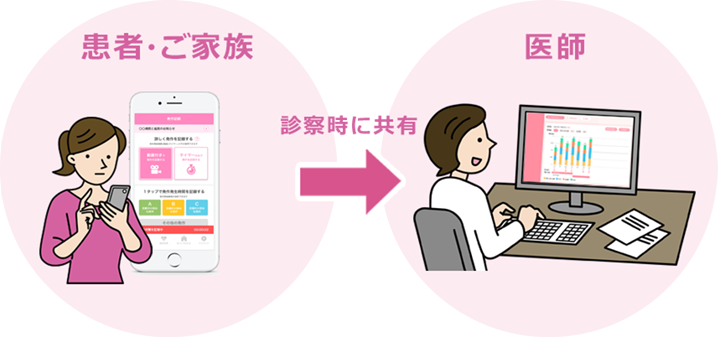

診察室では見えない、暮らしの中の患者・ご家族

自宅での自然な様子の把握による、実態に即した診療への活用が可能です。

の特徴患者・ご家族の主観的な訴えや生活状況などのPHRデータが診断や治療に効果的

患者さんと発作の動画を一緒に見たり、”この薬の時にはこういう発作があったね” などを共有しながら診察できるので、とてもコミュニケーションが進みます。